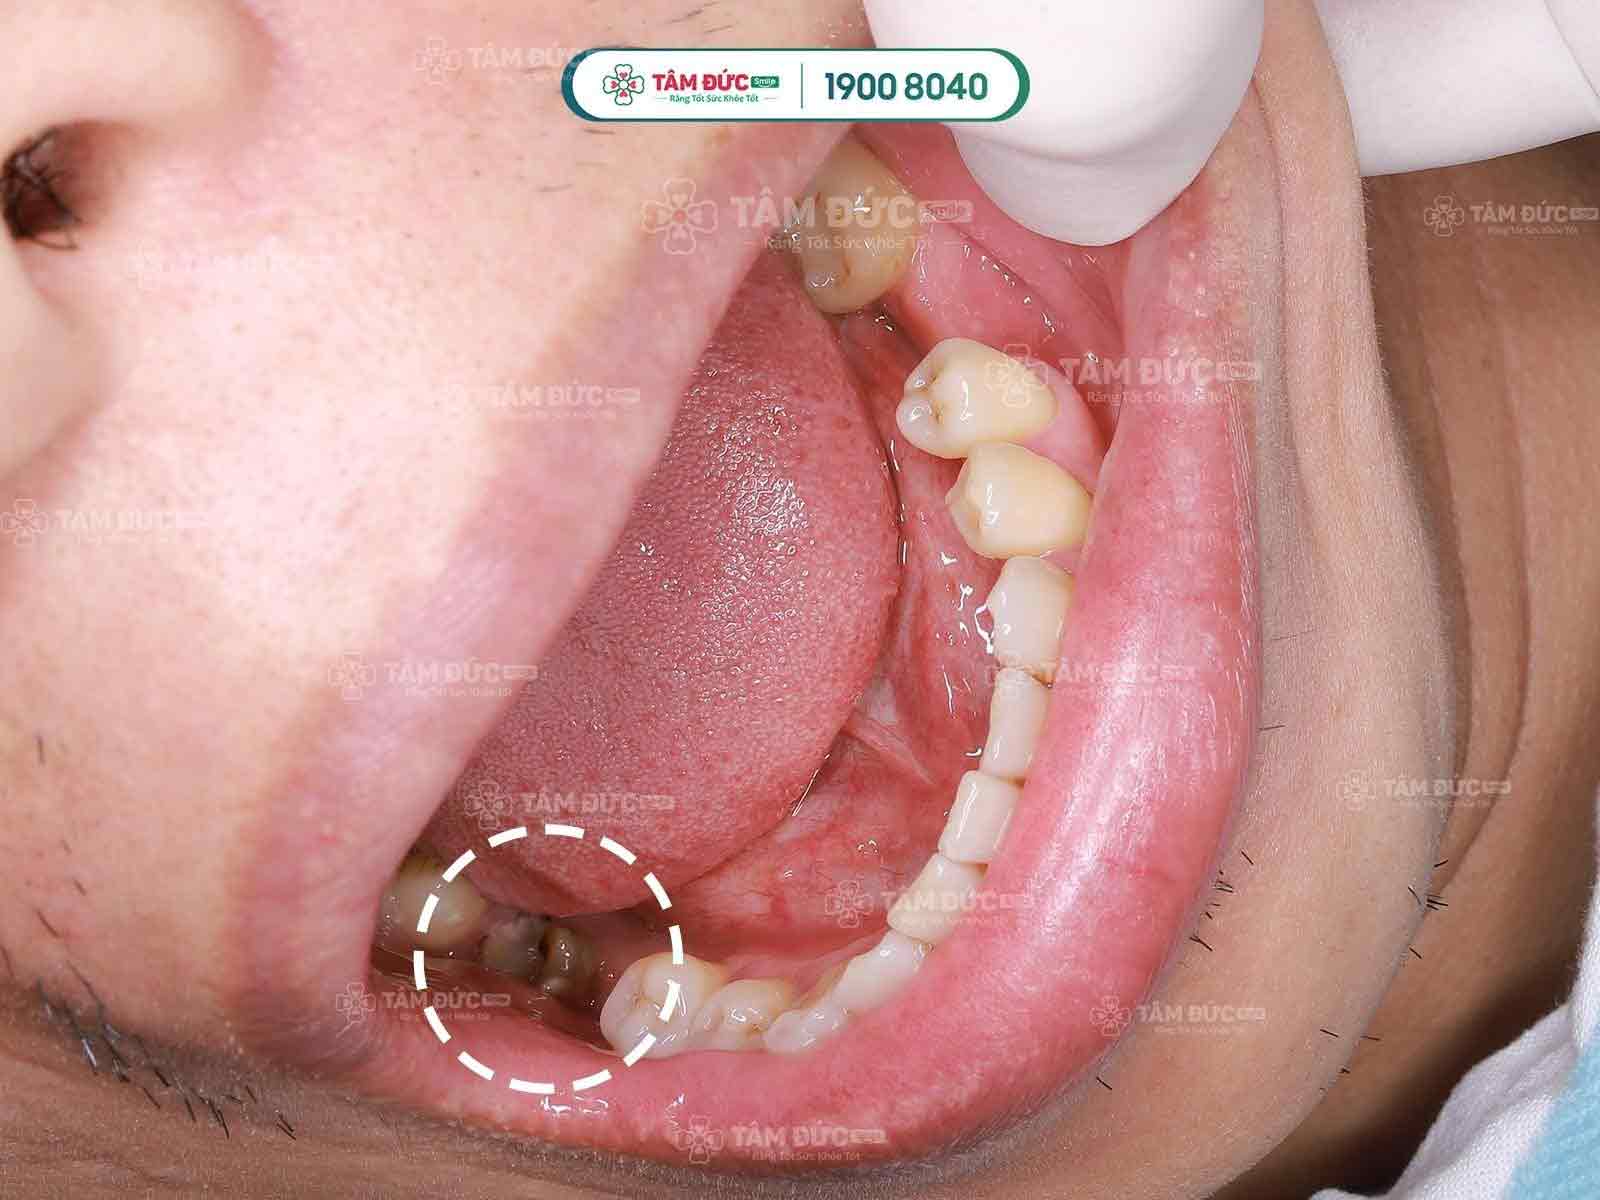

- Sâu răng: Khi bệnh sâu răng phát triển nặng và không được điều trị kịp thời, vi khuẩn sẽ tấn công vào cấu trúc bên trong răng, đi vào trong tủy răng, dẫn đến viêm tủy. Ban đầu chỉ là những triệu chứng nhẹ, nhưng về lâu dài, các vi khuẩn sâu răng sẽ làm viêm tủy răng và dẫn đến tình trạng hoại tử, làm chết tủy và phá hủy cấu trúc răng.

Các nguyên nhân gây ra viêm tuỷ